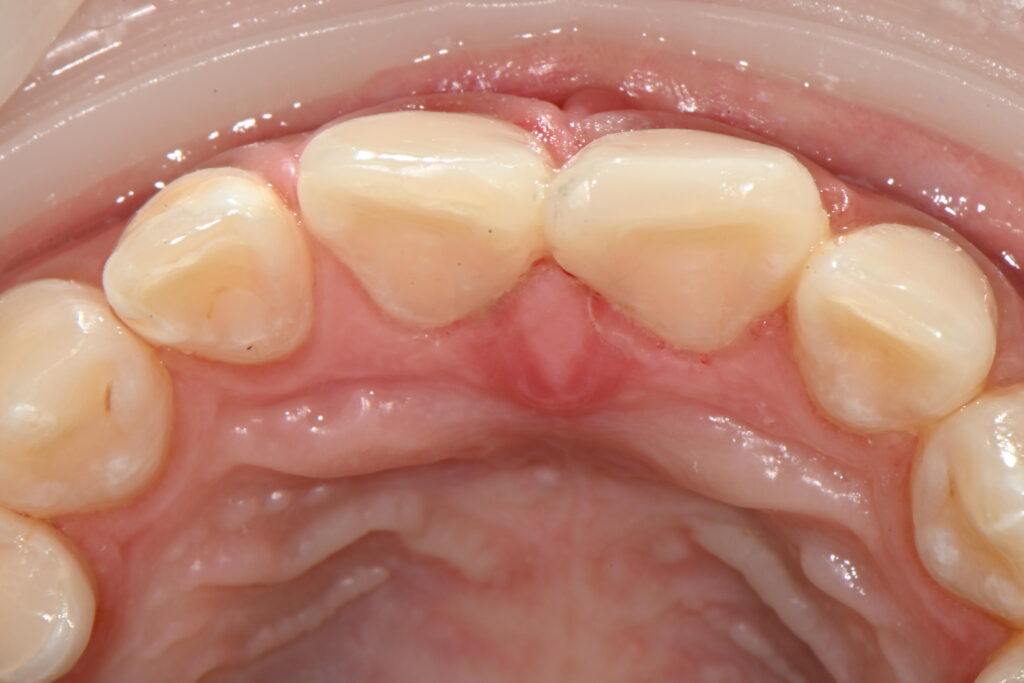

가장 중요한 뒷쪽 치아의 모습

앞쪽 치아의 모습도 중요하지만

이런 치료의 경우 뒷쪽 치아의 모습도 중요합니다

많은 분들이 치료를 받고 뒤에가걸린다

혀에 걸린다 이런 불편함을 호소하는 분들이 있는데요

레진 치료의 중요점은

안쪽 보이지 않는 부분을 치아와 같은 모습으로 충전하는 부분입니다

치료 전후 앞쪽과 뒷쪽을 확인하여

완전히 치아의 형태를 재현하였는지 확인을 해야 합니다

치료전후를 보면

뒷쪽까지 완전히 충전이 되면서

치아의 모양을 재현하였습니다